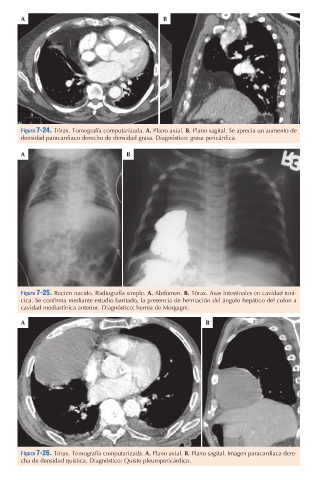

Figura 7-24. Tórax. Tomografía computarizada. A. Plano axial. B. Plano sagital. Se aprecia un aumento de

densidad paracardiaco derecho de densidad grasa. Diagnóstico: grasa pericárdica.

Figura 7-25. Recién nacido. Radiografía simple. A. Abdomen. B. Tórax. Asas intestinales en cavidad torá-

cavidad mediastínica anterior. Diagnóstico: hernia de Morgagni.

Figura 7-26. Tórax. Tomografía computarizada. A. Plano axial. B. Plano sagital. Imagen paracardiaca dere-

cha de densidad quística. Diagnóstico: Quiste pleuropericárdico.